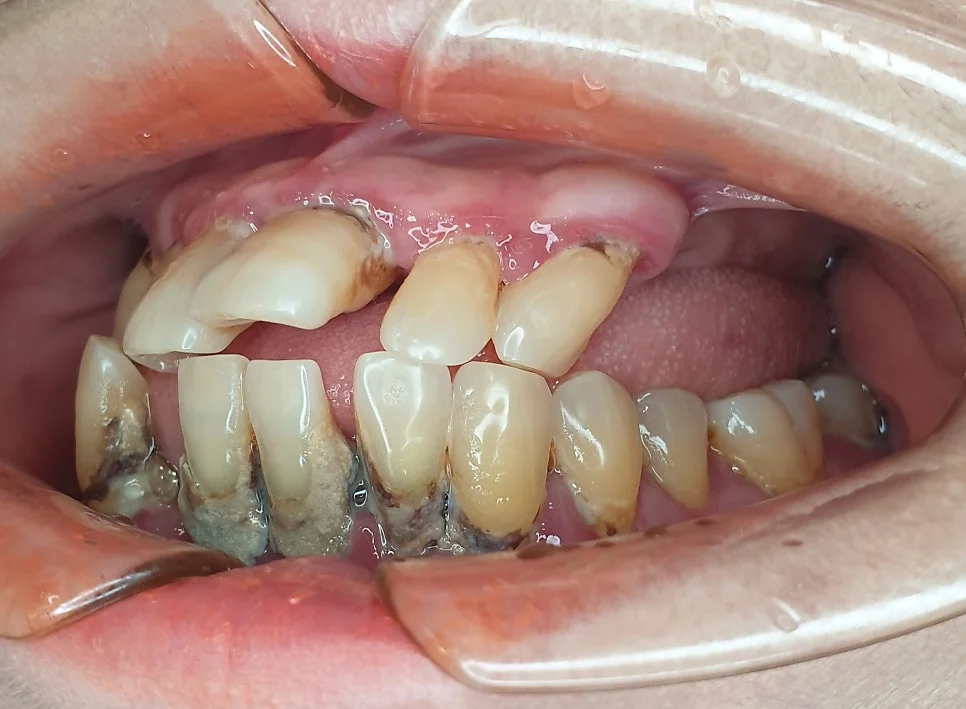

치료 전 (Before)

어금니를 조기에 상실하게 되면 상대적으로 앞니가 많은 힘을 받게 되고, 이로 인해 앞니가 버티지 못하고 흔들리게 되는 경우가 많습니다ㅜ

많은 치석과 치조골의 소실로 대부분의 치아를 발치해야 하며 임플란트 식립이 필요합니다. 보통 많은 치아의 발치 및 임플란트가 계획된 경우 위아래 두 번에 걸쳐 임플란트를 식립하게 됩니다.